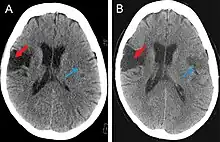

Scanning techniques include EEG, SPECT, MRI, and CT brain scanning.[1][2] These additional techniques are useful in determining what type of lesion the patient has, and allows physicians to determine more effective ways in treating the patient.

CT scan

This computer-tomography type of imaging is one of the most used in any clinical environment and although it can detect some of the brain areas affected by a stroke or a trauma it does not provide the same acuity as the magnetic resonance imaging. CT scans can also reveal, in patients with the syndrome, the bilateral cortical infarcts located in the posterior frontal region involving the opercular areas.[3]